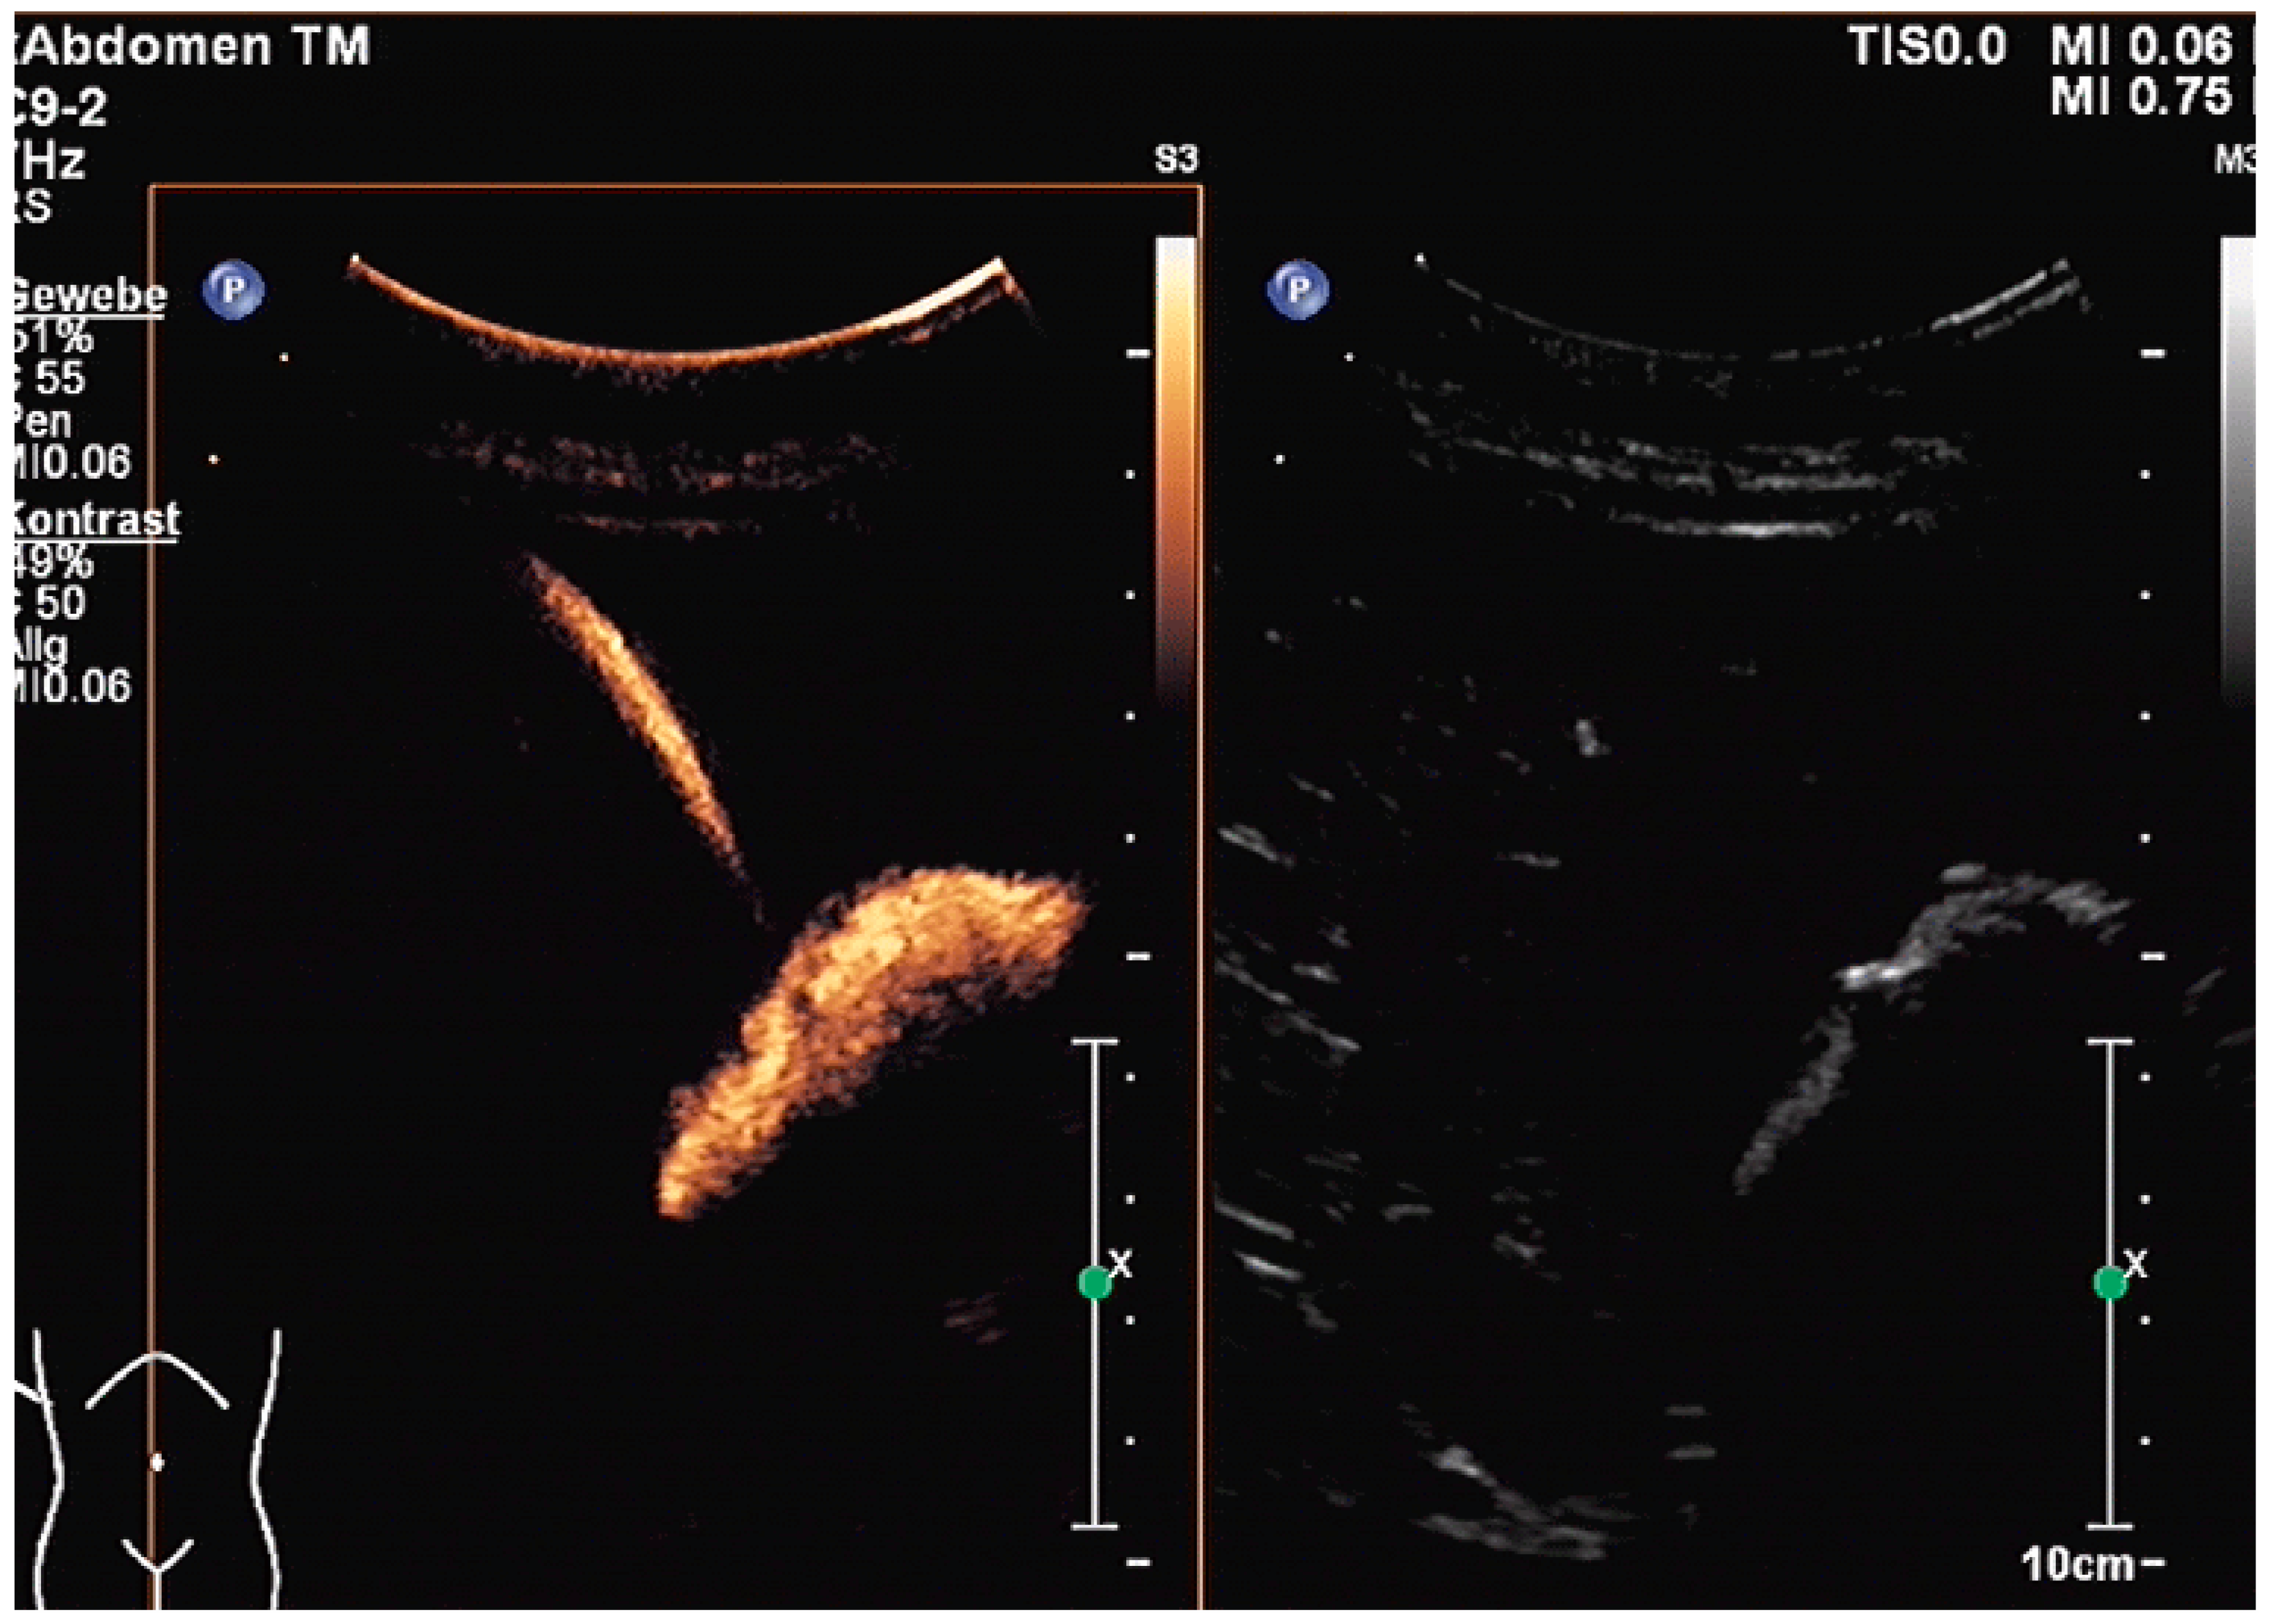

The aims of PGBD are the relief of symptoms and the disappearance of inflammation. If these criteria are met, the drainage can be removed. After pre-existing GB perforation, the integrity of the gallbladder wall should be documented. This can be performed very well by the injection of US-contrast agents (Figure 12 and Figure 13) [80].

Figure 12.

After injection of one drop of SonoVue® diluted in 10 mL sodium chloride 0.9% via drainage, gallbladder perforation and leakage can be excluded. Only the drain and the gall bladder lumen show enhancement (left side: low-MI-mode, right side: conventional grey-scale image).

Figure 13.

Gall bladder perforation. After injection of diluted US-contrast agent via the drain, contrast media appears at the lower liver surface. The drain was left in place for a few more days until surgery could be performed.

After the injection of one drop of SonoVue®, e.g., diluted in 10 mL sodium chloride 0.9% via the drain, gallbladder perforation and leakage can be excluded when only the drainage and the gall bladder lumen show enhancement, and no extravasation is observed.